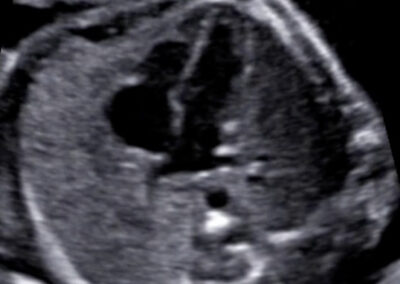

Dear future mother, we provide both basic and specialized ultrasound scans in pregnancy. We use Samsung’s state-of-the-art ultrasound systems and all our doctors are holders of Fetal Medicine Foundation certificates for all types of ultrasound examinations in pregnancy. We follow FMF protocols for fetal examinations and combine 2D with 3D ultrasound scan and assess even subtle anatomical details in order to obtain as precise a result as possible. Throughout the scan, we will keep you informed about the parts of fetal anatomy displayed on the screen. After the scan we will explain to you the results, prognosis and possible further management.

Specialized scans

Genetic ultrasound Fetal echocardiography Doppler assesment of feto-placental circulation Screening for preterm delivery Screening for pre-eclampsia and fetal growth restriction Multiple pregnancy 3D-4D scan Gender scan